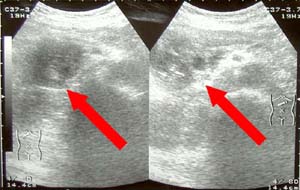

エコーで診察 |

膵臓がん エコー画像 |